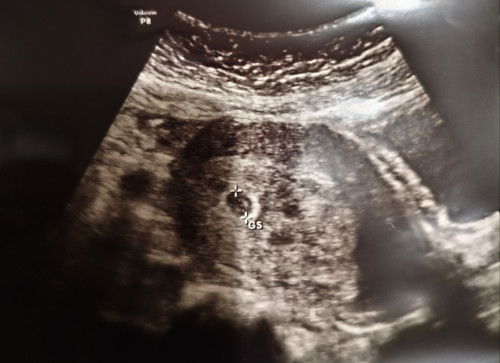

bun, km hasil usg nya ky gini ga bun? aku usg usia kandungan 5w, tp pas usg, dokternya ga blg apa2. aku pun jg ga tanya, ga engeh karena masih shock kalau ternyata hamil. sampai rmh baru bingung ko buletannya ada 3🙏